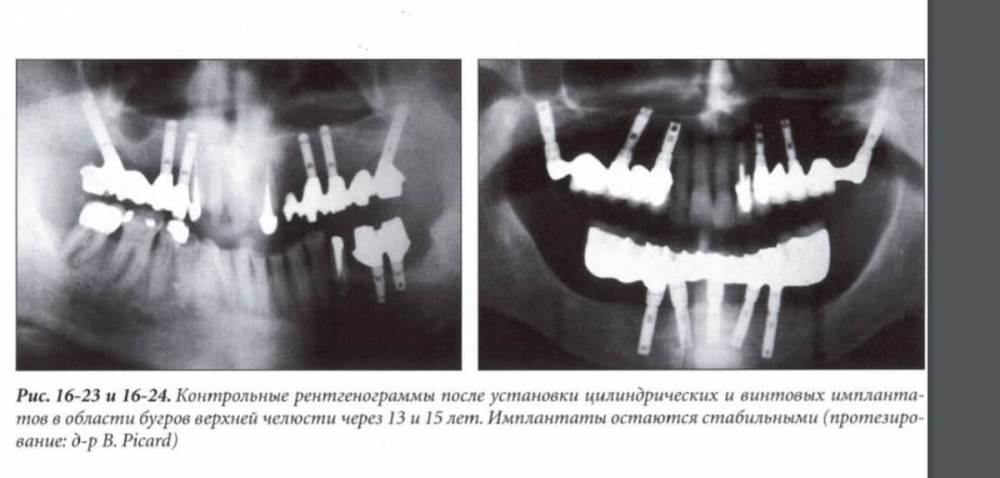

It'sGeorgy Опубликовано 31 января, 2022 Поделиться Опубликовано 31 января, 2022 @Карен Аванесов как вы вовремя подняли тему) На днях наткнулся на книжку Марка Бера 2007 года, так там этот метод имплантатов под наклоном в бугры уже описан и речь идет про наблюдение в 15 лет. Мы живем в интересном мире: вещи, которые описаны в 80-90х, но представленные на конгрессах только сейчас, кажутся иногда чем-то новым и инновационным. 3 Ссылка на комментарий

Карен Аванесов Опубликовано 31 января, 2022 Автор Поделиться Опубликовано 31 января, 2022 все новое придумано из старого, кто первый вспомнил тот и автор) первопроходцам было сложнее, бросать вызов. Влюбом случае выигрывает пациент, если врач рассматривает все возможные варианты 2 3 Ссылка на комментарий